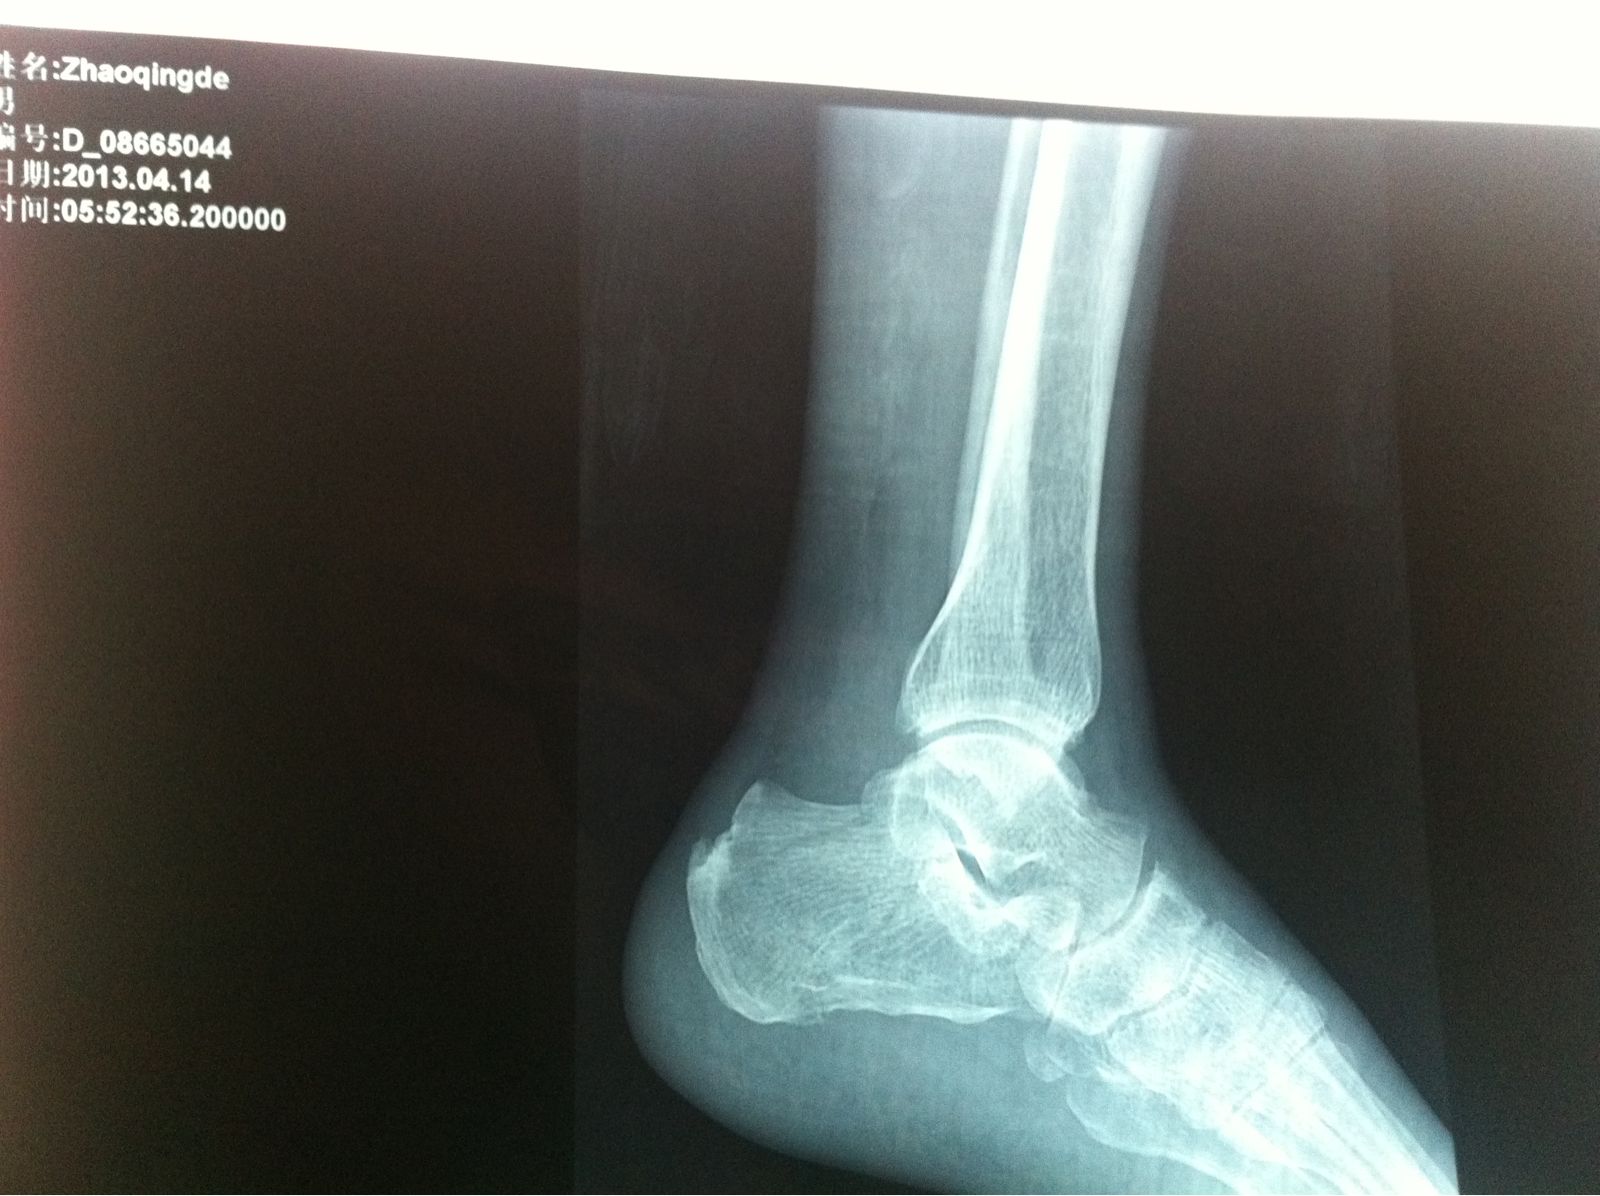

病人: 男 - 66岁 -林源人士 、

病因:蹦跳时脚受伤 -

病情;双脚后跟骨裂 - 左脚两处、 右脚一处 -